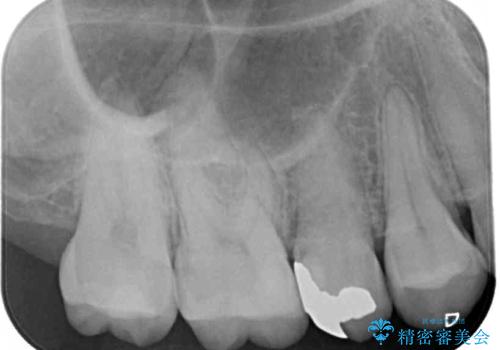

- 奥歯の銀歯の下にあるむし歯治療を希望して来院された患者様です。

口を開けたときに見えてしまう部分はセラミックインレーやジルコニアクラウンに、目立たない部分はゴールドインレーにてむし歯治療を行うこととしました。

機能面を優先すると、PGAインレー(ゴールドインレー)による修復治療やPGAクラウンによる補綴治療が望ましいのですが、笑ったときに見えている銀歯がどうしても気なってしまうとのことで、目立ってしまう奥歯はセラミックインレーやセラミッククラウンを装着することとしました。